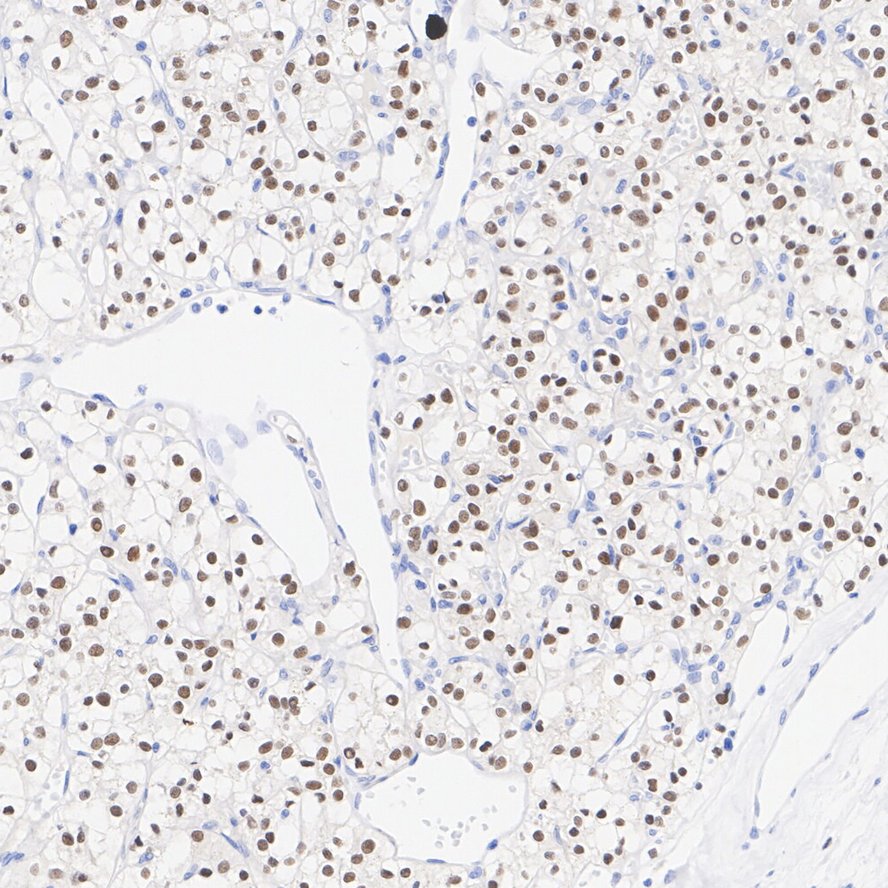

Immunohistochemical analysis of paraffin-embedded human renal clear cell carcinoma tissue with Rabbit anti-Pax2 antibody (ET1701-23) at 1/50 dilution.

The section was pre-treated using heat mediated antigen retrieval with Tris-EDTA buffer (pH 9.0) for 20 minutes. The tissues were blocked in 1% BSA for 20 minutes at room temperature, washed with ddH2O and PBS, and then probed with the primary antibody (ET1701-23) at 1/50 dilution for 1 hour at room temperature. The detection was performed using an HRP conjugated compact polymer system. DAB was used as the chromogen. Tissues were counterstained with hematoxylin and mounted with DPX.